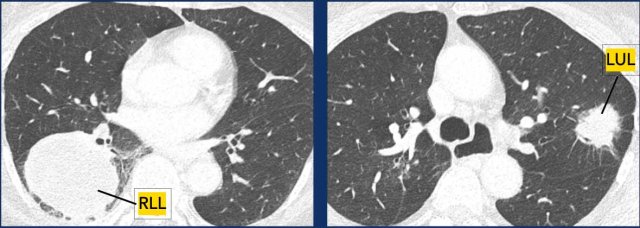

Figures

This was a T4N0M0 in RLL.

This was a T2bN1M0 in LUL